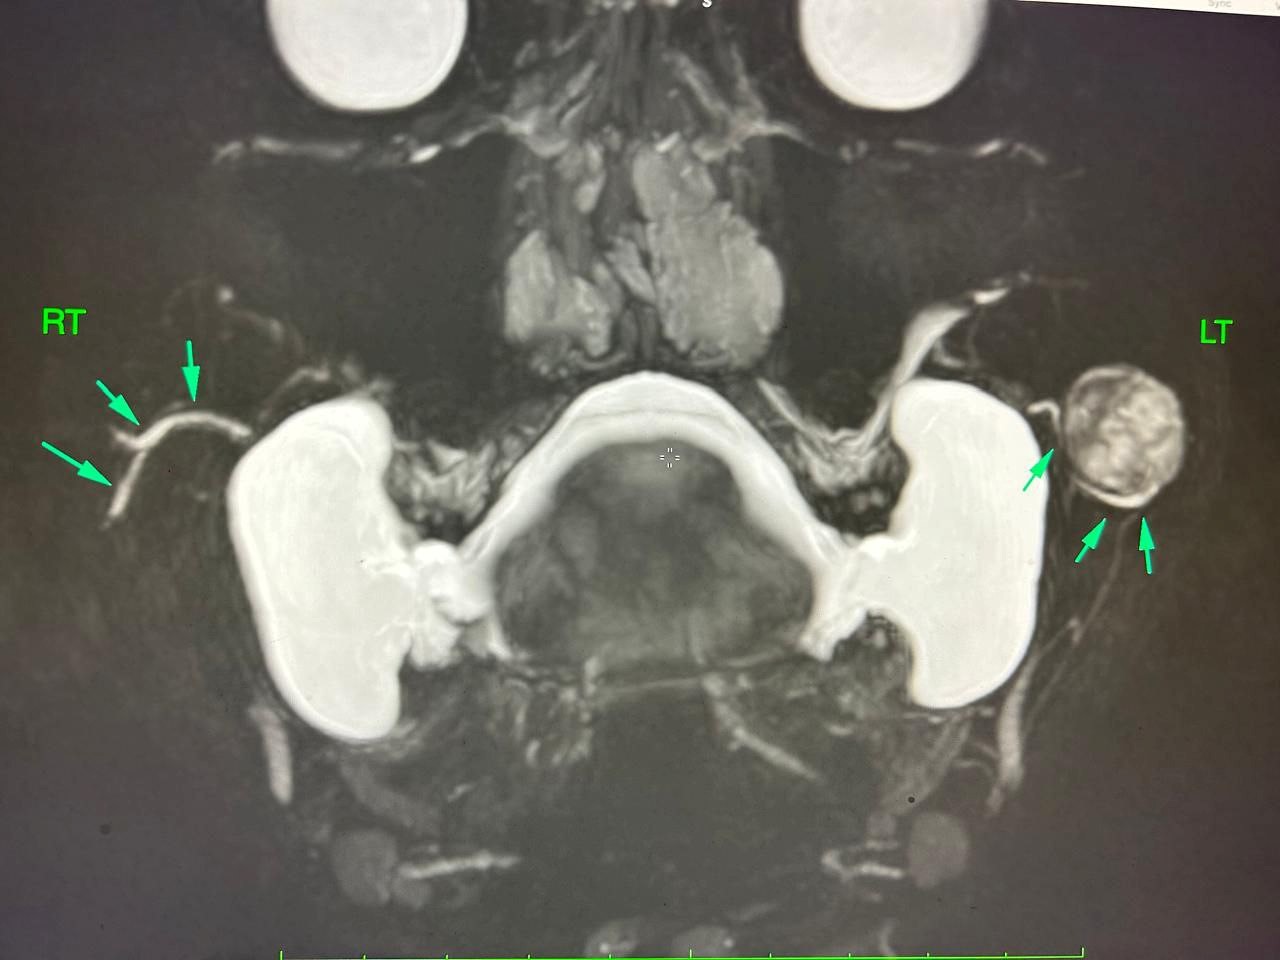

MRI (Neck and Parotid Gland):

A well-defined ovoid lesion measuring 2.0 × 1.6 × 1.3 cm in the left cheek region, hypointense on T1 and heterogeneously hyperintense on T2-weighted images with few cystic foci. The lesion arose exophytically from the anterior portion of the left parotid gland, deep to the buccinator and superficial to the anterior masseter. The parotid duct was displaced inferomedially but remained patent with no proximal dilatation. No deep lobe extension or perineural spread was observed.

Impression: Imaging features consistent with pleomorphic adenoma.